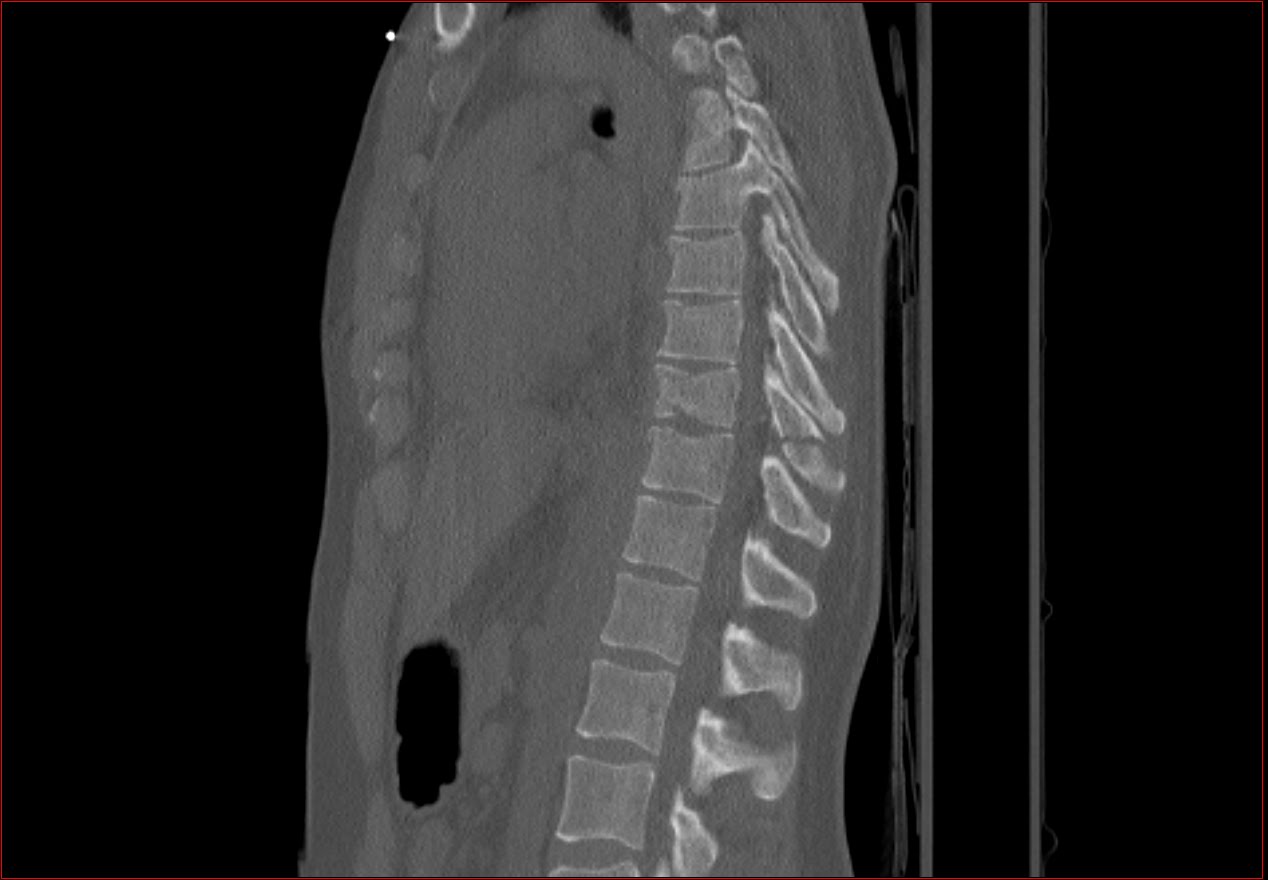

Csigolyatores a thoracalis gerincszakaszon Szerző: admin | jún 10, 2010 | Fracture, Pneumothorax, Trauma | Nincsenek hozzászólások A csigolyatest felso zarolemezt is erinto elulso torese tores a processus spinosuson